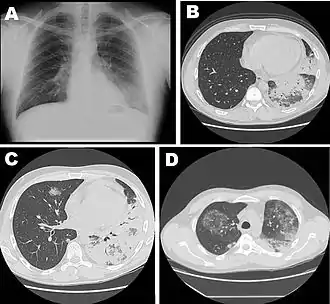

| Chest X-ray of a severe case of legionellosis upon admission to the emergency department. | |